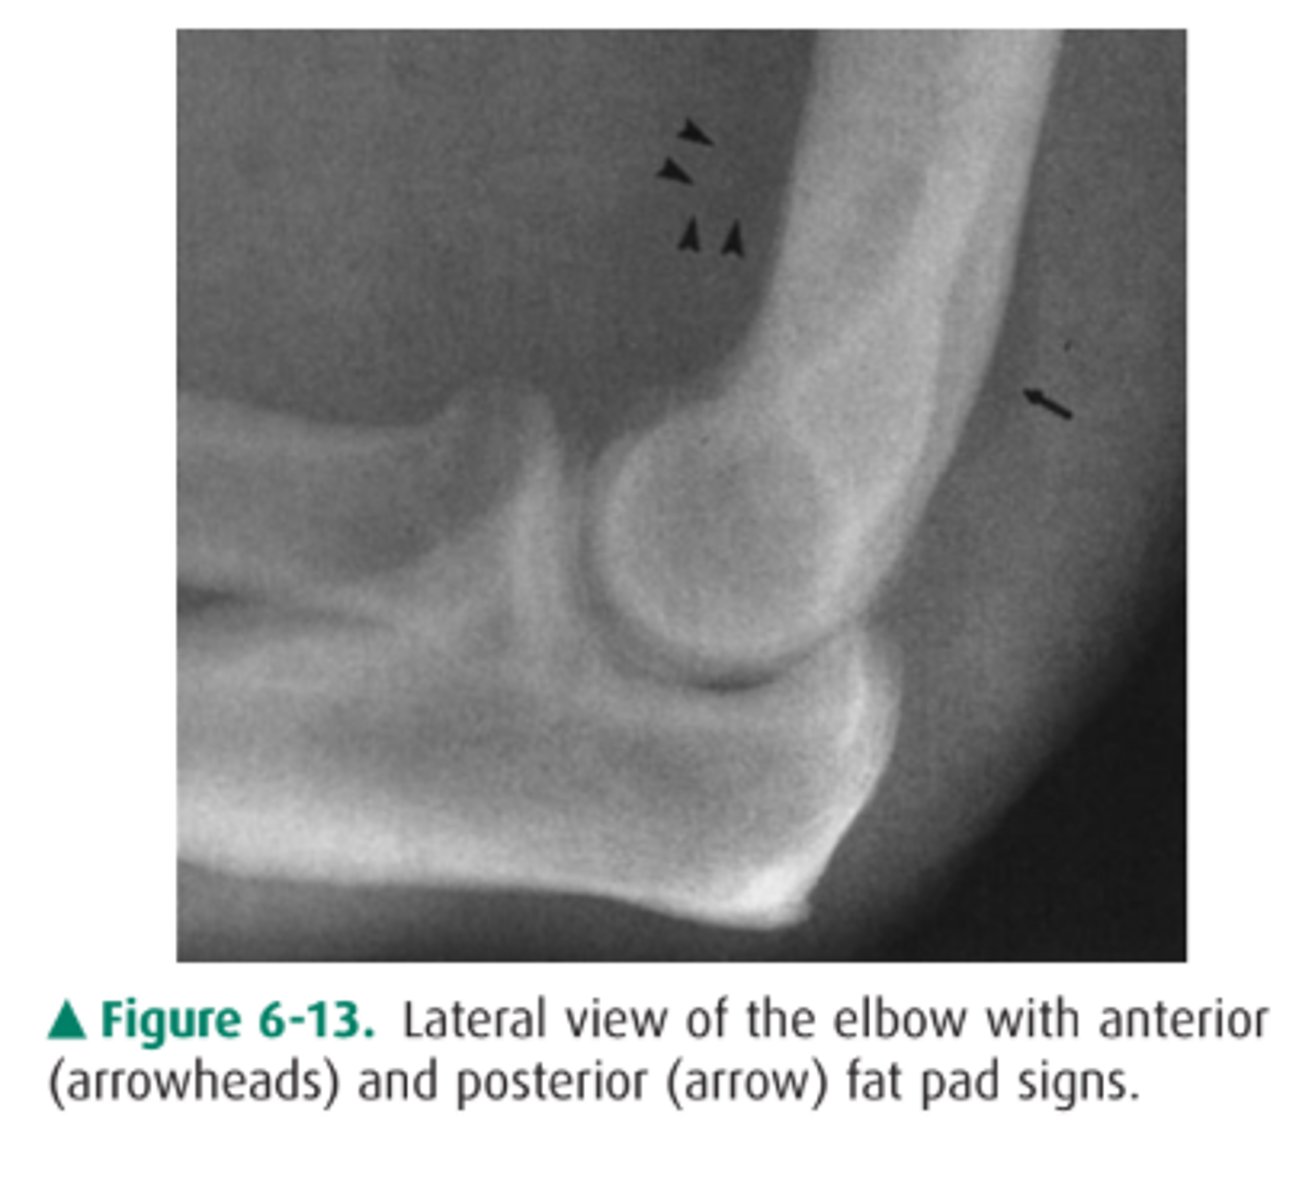

While moonlighting in the emergency department of a small community hospital, you examine a 25-year-old man who fell on an outstretched

hand and now complains of elbow pain. You obtain an AP and lateral view of his elbow (lateral view of the elbow).

You first examine the lateral view of the elbow in Case

6-3 (Figure 6-10). You find

A. a lytic lesion in the distal humerus.

B. displacement of the fat pads of the elbow.

C. a fracture through the proximal ulna.

D. dislocation of the elbow.

Answer

B.

You have the anterior sail sign and posterior fat pad sign.

What causes the anterior and posterior fat pads?

Displacement due to accumulation of blood or fluid in underlying tissues

Examples of what can cause the fat pad appearance

-Rheumatoid arthritis

-bleeding disorder

-Radial head fracture